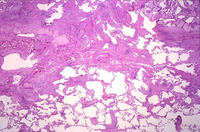

Pathology slide of usual interstitial pneumonia, the characteristic biopsy appearance of a patient with idiopathic pulmonary fibrosis

From the collection of Gregory Tino, MD; used with permission